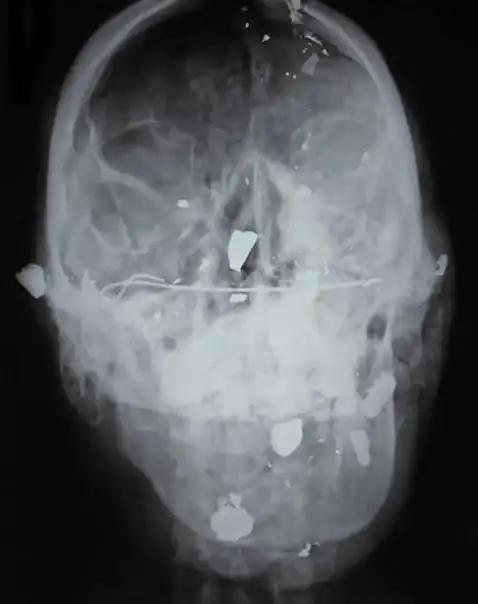

Убийство. Множественные выстрелы в голову.